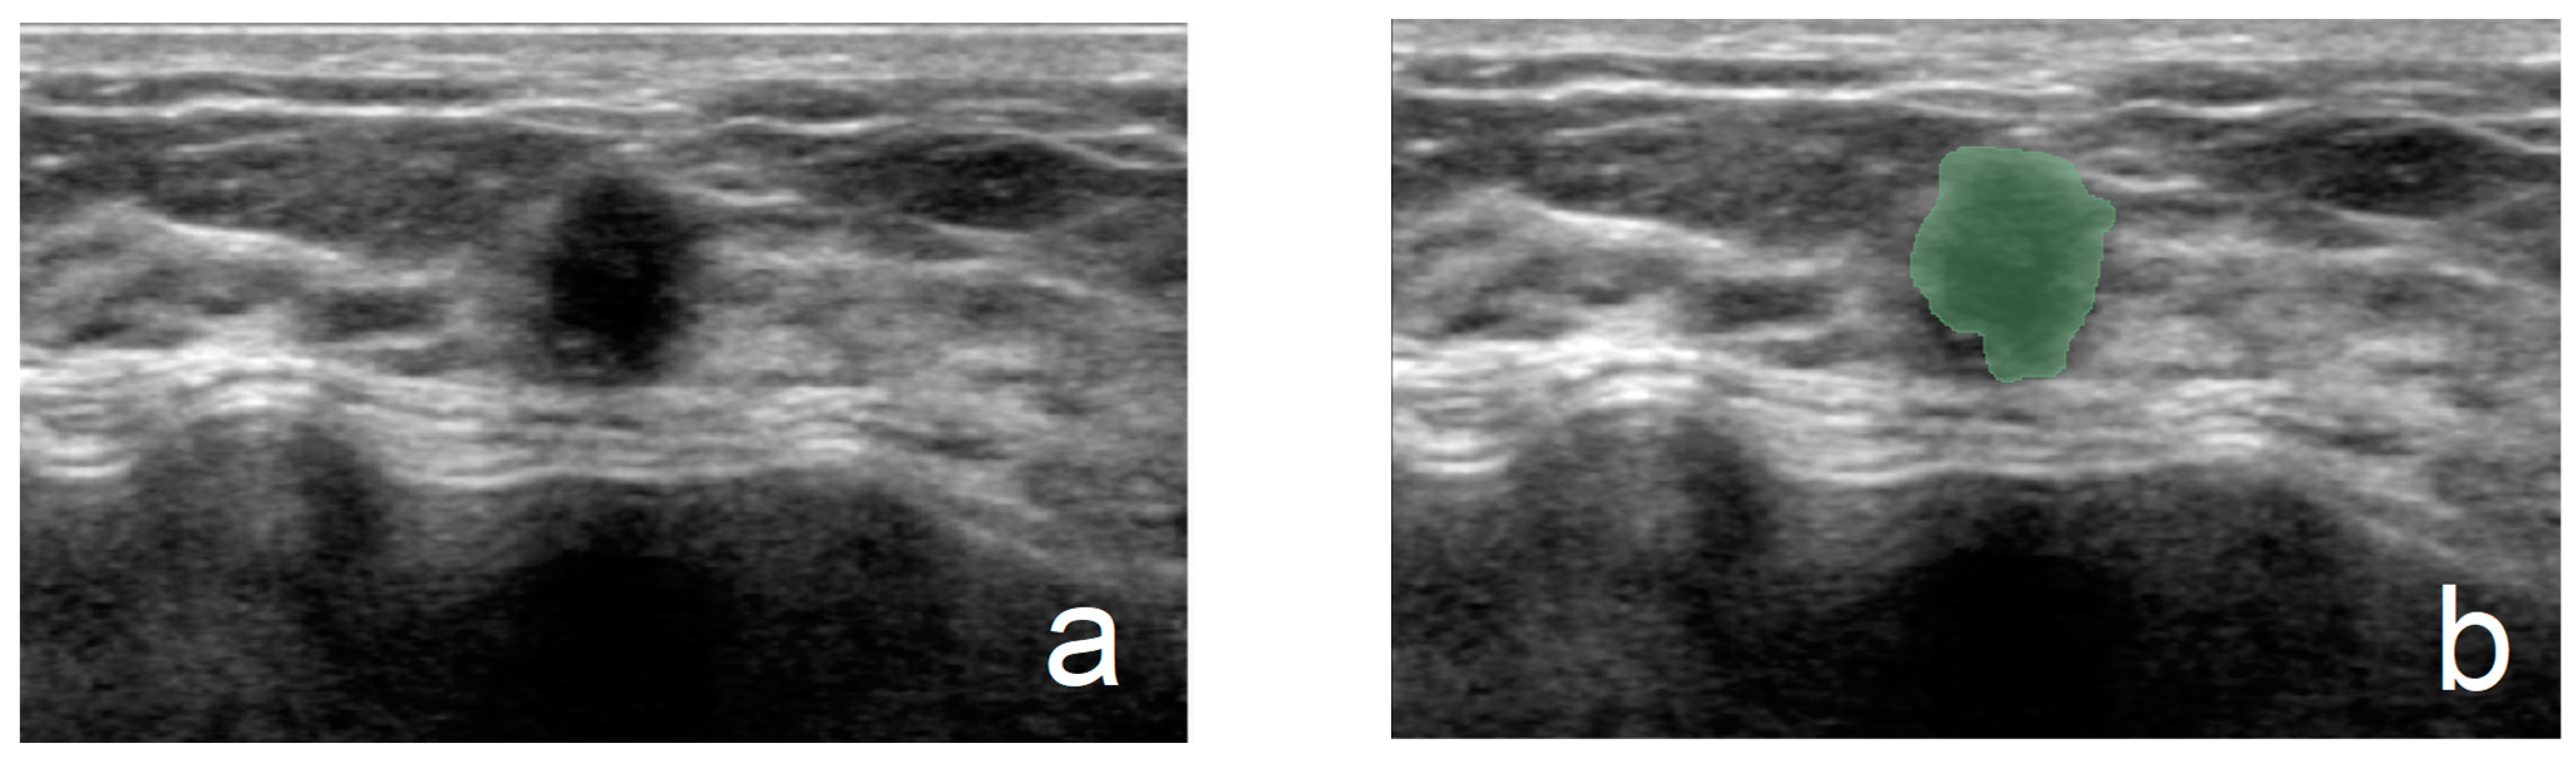

2.4. Acquisition of Ultrasound Pictures, Preprocessing, and ROI Delineation